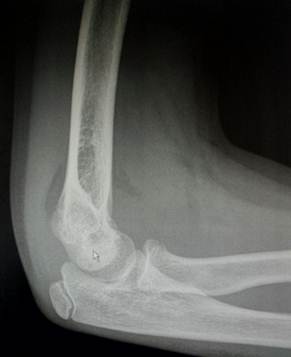

11- 13 лет

Это возраст, в котором все ядра окостенения достигли максимального

развития и приняли формы соответсвующих образований. На рентгенограммах их

разделяют узкие полоски ростковых зон. Это максимальный расцвет детского локтя.

Возраст

12 лет. Все ядра окостенения локтя развиты и разделены узкими хрящевыми

прослойками. Вершина локтевого отростка содержит основное ядро окостенения и

ядро – спутник неправильной формы.

14 лет. Стремительное закрытие зон роста локтевого сустава. Можно заметить

узкие просветы в основании медиального и латерального надмыщелков, а также пока

еще открытую зону роста в локтевом отростке.

Иногда

трудности с интерпретацией рентгенологической картины локтевого сустава

возникают даже у многоопытных специалистов. И что тогда делать? – Надо сделать

рентгенограммы противоположного, здорового сустава и сравнить. Но в большинстве

случаев внимательное изучение анамнеза, клинической картины и рентгенограммы

позволяет принять правильное решение и без этого.

Мы

думаем, что все, кто имел дело с детской травмой, согласятся с нами, что для

детей являются типичными переломы нижнего конца плечевой кости: чрезмыщелковые

переломы, переломы головчатого возвышения и блока, переломы надмыщелков.

Причиной тому является обилие хрящевой ткани в составе нижнего конца плечевой кости

и нежность структур, которые она формирует. По своей сути это даже не переломы,

а остеоэпифизеолизы. Механизм травмы простой – падение с упором на руку. Да,

может произойти перелом дистального отдела лучевой кости подобно тому, как это

бывает у взрослых. Но там хрящ достаточно толстый и мощный, не так-то просто

его сломать. А вот локоть… Дети в возрасте от 3 до 12 лет именно его и ломают.

Переломы в области локтя у детей пользуются дурной славой: ими пугают

родителей, ими гордятся врачи и пугают других врачей, не знакомых с этой

травмой. А на самом деле они легко репонируются, если это вообще требуется,

легко фиксируются и быстро срастаются за 2 недели! Для получения хорошего

результата требуется две вещи: знания и здравый смысл.